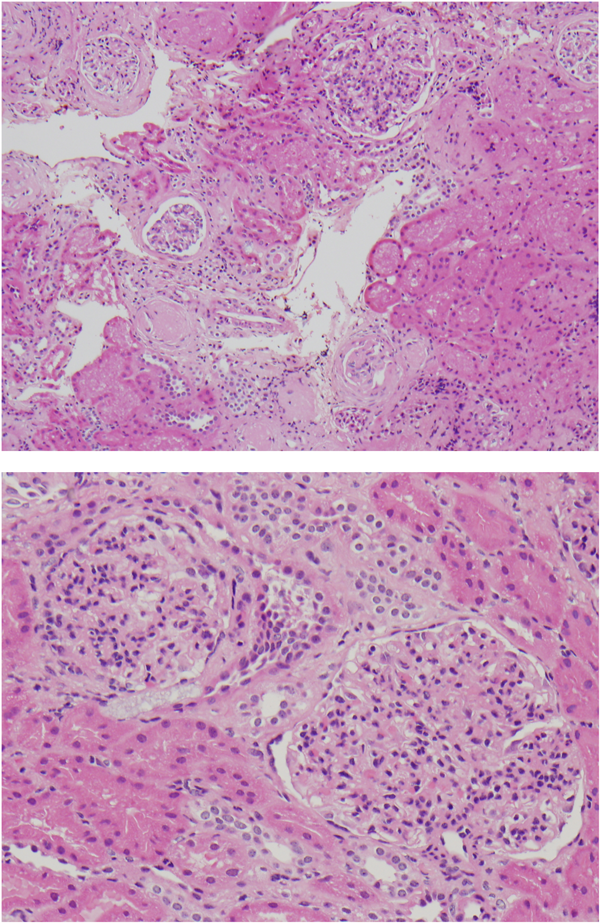

8)腎臓合併症

チアノーゼに起因する腎障害はチアノーゼ腎症(cyanotic nephropathy)といわれ,軽微な蛋白尿であることが多いが,時としてネフローゼ症候群や慢性腎不全をきたすこともある.糸球体静水圧上昇と基底膜の透過性亢進により蛋白尿が生ずる.

病理学的には糸球体の肥大,糸球体毛細管の増生と拡張,メサンギウム細胞増殖,メサンギウム基質の増加,メサンギウム融解,傍糸球体細胞の増殖,輸入細動脈の拡張,分節性硬化所見など,糸球体病変が主で,尿細管の異常は軽微である(図7).赤血球増多による血液粘稠度上昇に伴ううっ血と,前述の末梢血管の拡張と増生がその主因であるが,心疾患に伴ううっ血性心不全,糸球体にトラップされた骨髄巨核球とその産生物質であるPDGF(platelet derived growth factor)やTGF(transforming growth factor)の影響も示唆されている.またエリスロポイエチンによる血管新生もチアノーゼ腎症に関与する可能性も報告されている7–9)

Pediatric Cardiology and Cardiac Surgery 31(3): 95-101 (2015)

図7 チアノーゼ腎症の病理組織(HE浅色)

糸球体の腫大,メサンギウム細胞のびまん性増殖が認められる.